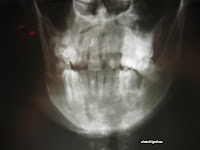

Terapi : Intraosseous interdental wiring (IOID)